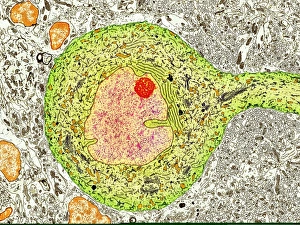

The central nervous system, the intricate network that governs our every thought and movement, is a marvel of complexity. From the delicate cerebellum tissue to the detailed light micrograph capturing its essence, we are reminded of its importance in maintaining balance and coordination. Anatomy comes alive as we explore the human brain from an inferior view. The intricacy of brain fibers is revealed through DTI MRI scans like C017/7099 and C017/7035, showcasing their vital role in transmitting information throughout this extraordinary organ. Artistic renderings bring us closer to understanding the medulla oblongata's significance within the brain. Its portrayal in various artworks allows us to appreciate how it controls essential functions such as breathing and heart rate. As we delve deeper into studying the central nervous system, models of the human brain provide invaluable insights into its structure and organization. Lateral views reveal countless regions responsible for cognition, emotion regulation, sensory perception, and motor control. Microscope slides offer glimpses into nerve cells' intricate architecture—a testament to their ability to transmit electrical signals at lightning speed. Meanwhile, glial stem cell cultures captured under a light microscope remind us of their crucial role in supporting neuronal function. Finally, artistic representations unveil the limbic system's enigmatic nature—an interconnected web responsible for emotions and memory formation. These captivating artworks allow us to visualize this complex network within our brains. Exploring these hints provides a glimpse into the awe-inspiring world of our central nervous system—the very foundation upon which our thoughts, actions, memories reside—reminding us just how remarkable our brains truly are.